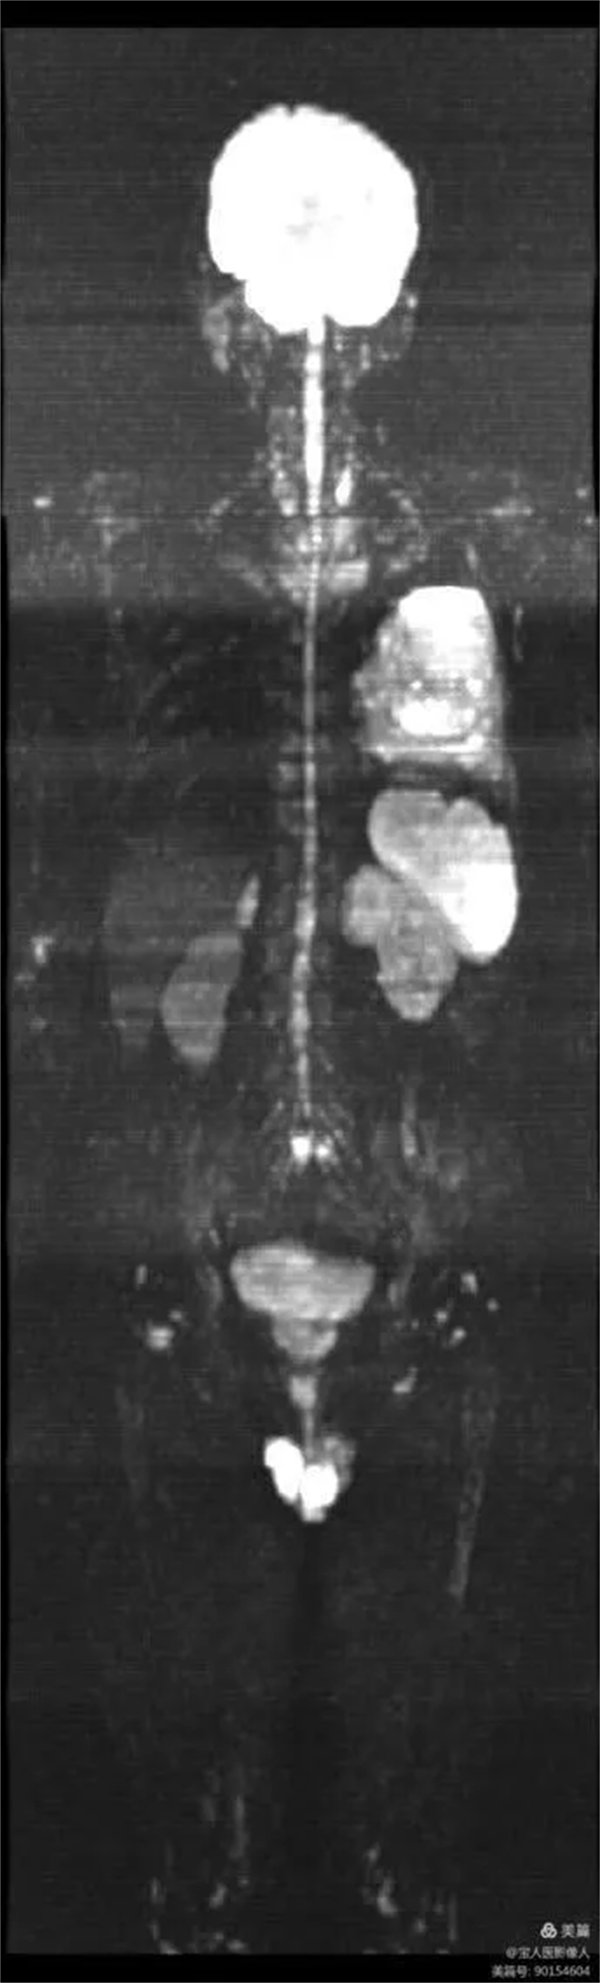

患者,男,左肺病變,為了查找全身有無其它病灶,明確分期,制定最合適的診療方案,臨床醫生決定行“類PET”即全身磁共振彌散成像(WB-DWI)檢查。

圖1:全身彌散成像圖像

磁共振全身彌散加權成像(WB-DWI),是將彌散加權成像技術與自動拼接技術和全景成像矩陣相結合而獲得全身的彌散加權成像影像。所得影像經黑白翻轉后可達到與正電子發射計算機體層顯像(PET)影像類似的效果,故被稱為“類PET”,是近年來發展起來的全新影像檢查新技術。

該技術能夠進行全身大范圍掃描,并加以3D后處理重建,可獲得全身腫瘤篩查、良惡性腫瘤的鑒別、腫瘤TNM分期及療效隨診等診斷信息,全身彌散技術把肌肉、脂肪、肝臟等組織背景信號抑制掉,突出了病變的顯示,大大提高了病變組織尤其是惡性腫瘤及其轉移灶的檢出率。